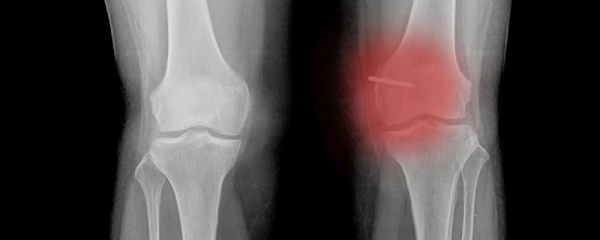

据统计,我国腰椎病患者已接近2亿,腰间盘突出症患者占全国总人数的15.2%,近些年来呈上升趋势,治疗不当或不及时会造成肢体麻木、小便失禁甚至终身瘫痪。与此同时,腰椎病发病明显趋向低龄化。

腰椎间盘位于两个椎体之间,是一个具有流体力学特性的结构,由髓核、纤维环和软骨板三部分构成,其中髓核为中央部分,纤维环为周围部分,包绕髓核,软骨板为上、下部分,直接与椎体骨组织相连,整个腰椎间盘的厚度为8mm~10mm。

腰椎间盘突出症主要是因为腰椎间盘各部分(髓核、纤维环及软骨板),尤其是髓核,有不同程度的退行性改变后,在外力因素的作用下,椎间盘的纤维环破裂,髓核组织从破裂之处突出(或脱出)于后方或椎管内,导致相邻脊神经根遭受刺激或压迫,从而产生腰部疼痛。

人体上部重量70%左右是由储存在椎间盘孔中的水分所支撑的。20岁以前腰椎间盘有血管分布,其后逐渐消失其水分含量也逐年降低,胎儿时纤维环和髓核的水分含量分别为80%和90%。30岁时分别降至60%和75%。

椎间盘从出生到我们走向生命的终点始终处在一个脱水的过程,也就是说随着我们年龄的增长椎间盘的含水量是越来越少的。水与循环相关,水与营养代谢相关,缺水就会造成椎间盘的老化,营养供应易不足,损伤不易修复。